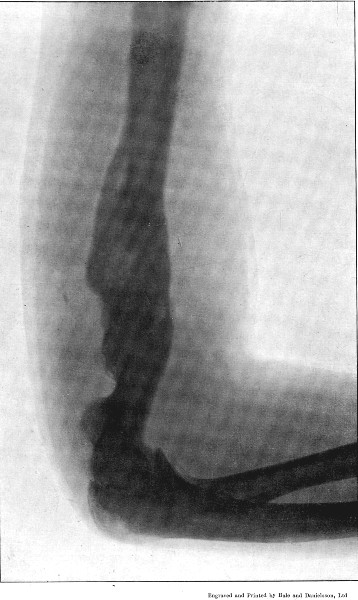

4. Comminuted Fracture of Shaft of Humerus180

5. Comminuted Fracture of Humerus accompanied by an Explosive Exit182

6. Comminuted Fracture of Humerus due to Oblique Impact184

7. Same Fracture healed186

8. Low Velocity Fracture of Humerus With Retained Bullet188